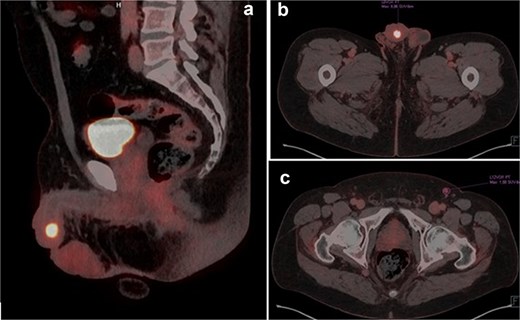

A 63-year-old male presented with a three-year history of reduced urinary flow and dysuria, developing urethral bleeding in the last 8 months prior to consultation. Two weeks before seeking care at our institution, he underwent holmium laser transurethral resection of a hardened papillomatous urethral lesion located in the navicular fossa. Pathological analysis revealed invasion by pure LELC of the urethra with involvement of the lamina propria (pT1). Advanced imaging studies, including penile MRI and FDG-18 PET-CT, demonstrated involvement of the glans and corpus spongiosum by the lesion (Fig. 1a–c).

(a and b) PET-TC FDG-18 showing hypermetabolic lesion in glans. (c) Left inguinal lymph node positive in PET-TC.